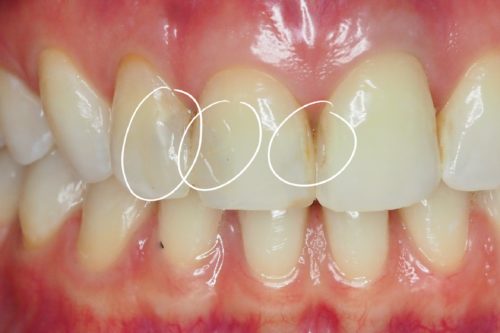

Pacjentka zgłosiła się z powodu licznych, nieszczelnych i nieestetycznych wypełnień w górnej dwójce

Usunięto stare wypełnienia, opracowano ubytki i wykonano estetyczną odbudowę korony zęba materiałem kompozytowym